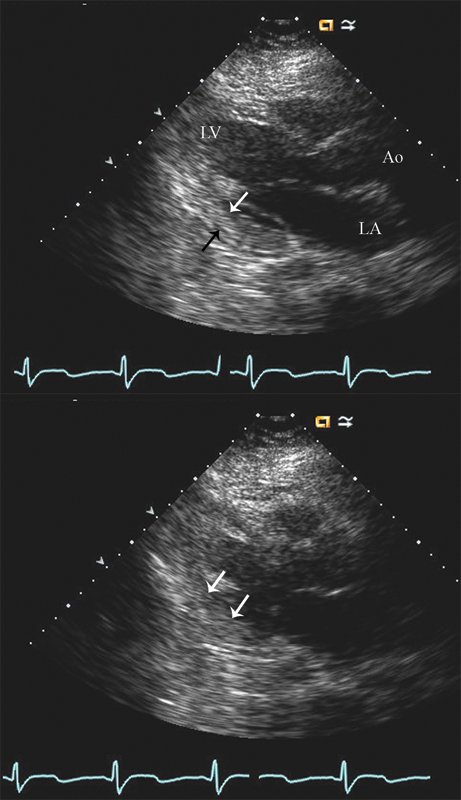

فحوصات تشخيصية لبعض امراض القلب والشرايين التاجية